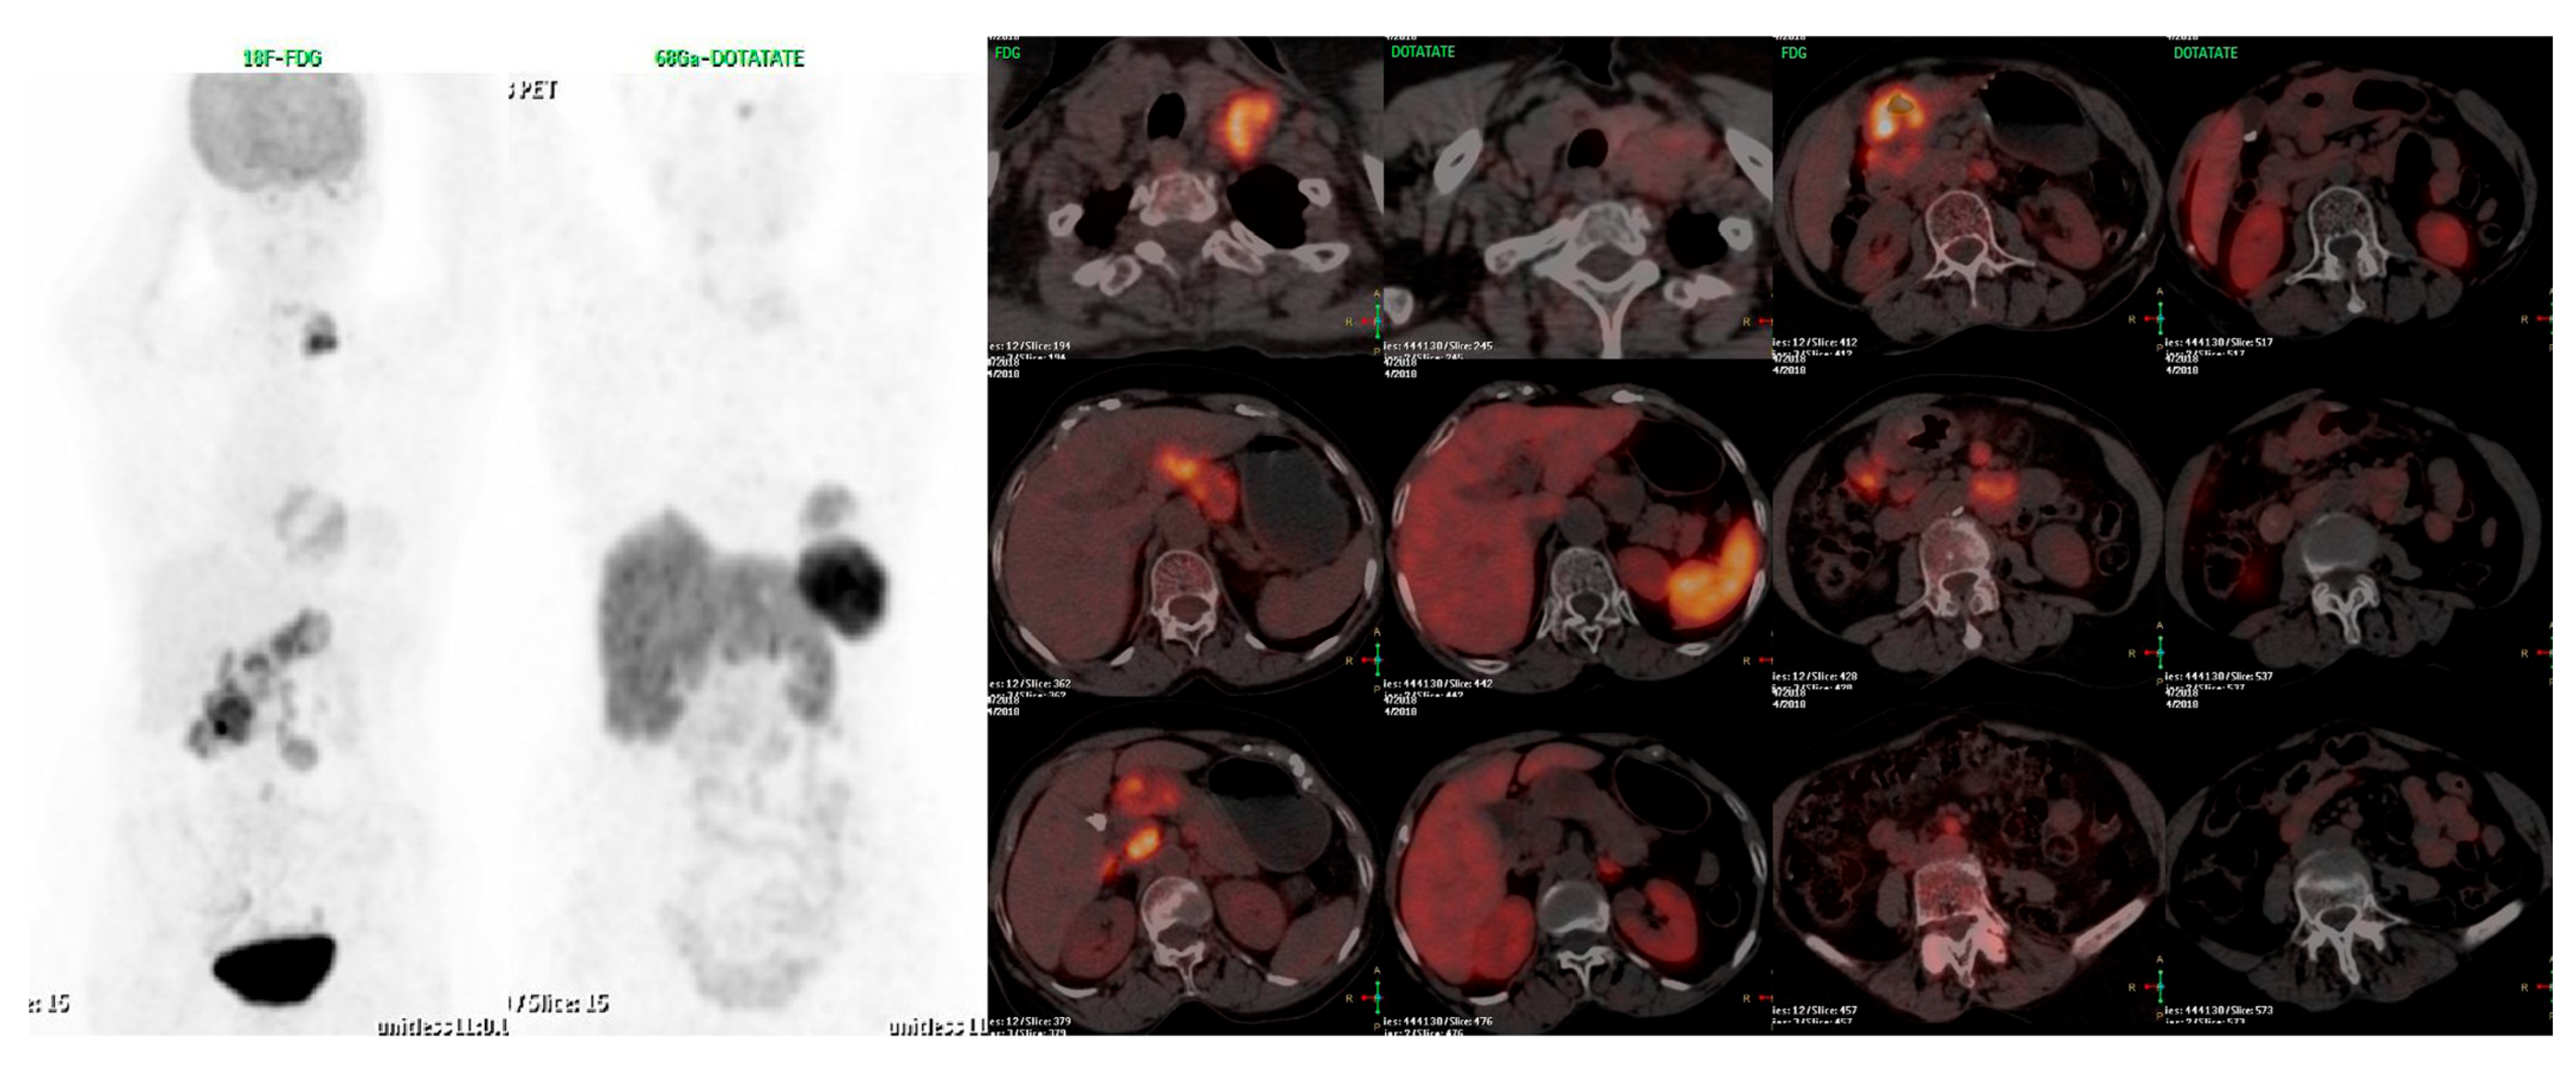

- Chan, D.L.; Pavlakis, N.; Schembri, G.P.; Bernard, E.J.; Hsiao, E.; Hayes, A.; Barnes, T.; Diakos, C.; Khasraw, M.; Samra, J.; et al. Dual Somatostatin Receptor/FDG PET/CT Imaging in Metastatic Neuroendocrine Tumours: Proposal for a Novel Grading Scheme with Prognostic Significance. Theranostics 2017, 7, 1149–1158. [Google Scholar] [CrossRef]

- Karfis, I.; Marin, G.; Levillain, H.; Drisis, S.; Muteganya, R.; Critchi, G.; Taraji-Schiltz, L.; Guix, C.A.; Shaza, L.; Elbachiri, M.; et al. Prognostic value of a three-scale grading system based on combining molecular imaging with 68Ga-DOTATATE and 18F-FDG PET/CT in patients with metastatic gastroenteropancreatic neuroendocrine neoplasias. Oncotarget 2020, 11, 589–599. [Google Scholar] [CrossRef] [PubMed]

- Chan, D.L.; Hayes, A.R.; Karfis, I.; Conner, A.; O’Mahony, L.F.; Mileva, M.; Bernard, E.; Roach, P.; Marin, G.; Pavlakis, N.; et al. Dual [68Ga]DOTATATE and [18F]FDG PET/CT in patients with metastatic gastroentero-pancreatic neuroendocrine neoplasms: A multicentre validation of the NETPET score. Br. J. Cancer 2023, 128, 549–555. [Google Scholar] [CrossRef]

- Adnan, A.; Basu, S. Discordance Between Histopathologic Grading and Dual-Tracer PET/CT Findings in Metastatic NETs and Outcome of 177Lu-DOTATATE PRRT: Does In Vivo Molecular PET Perform Better from the Viewpoint of Prediction of Tumor Biology? J. Nucl. Med. Technol. 2021, 50, 248–255. [Google Scholar] [CrossRef]